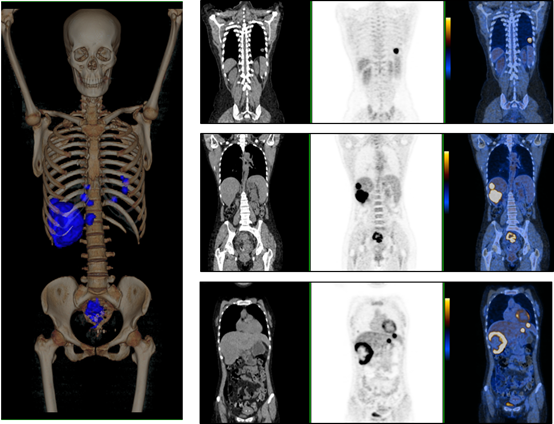

图一:快速低剂量PET/CT直肠癌探测

临床诊断及点评 本例患者直肠术后吻合口处软组织肿块,PET/CT体部检查显示18F-FDG代谢增高,伴右肺18F-FDG高代谢结节,提示转移。GE Discovery PET/CT 710业内最多PET探头,具有较高的灵敏度,其128层的CT可以降低患者辐射剂量。在保证图像质量的情况下,通过每床位1分钟重叠10%的快速扫描和低剂量注射,增加了医院的患者流通量;有效控制医疗费用,提高效益-成本比。